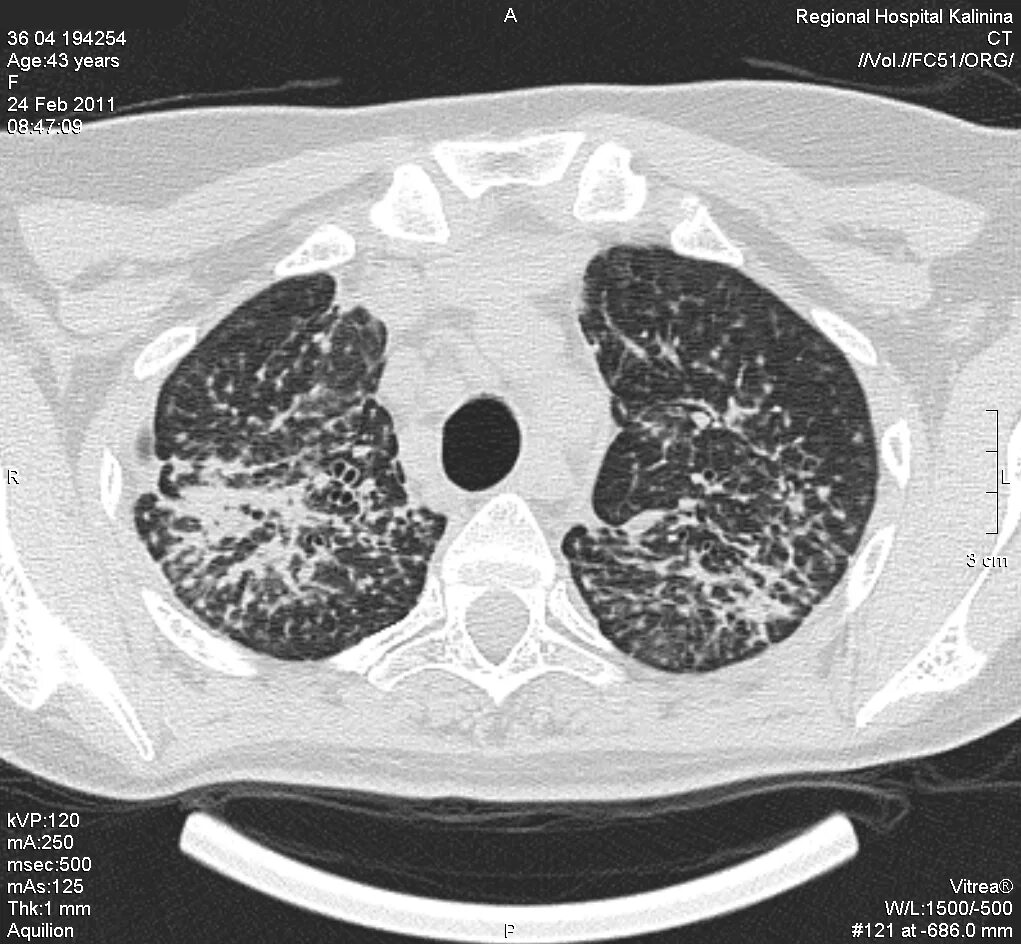

Фиброз кт